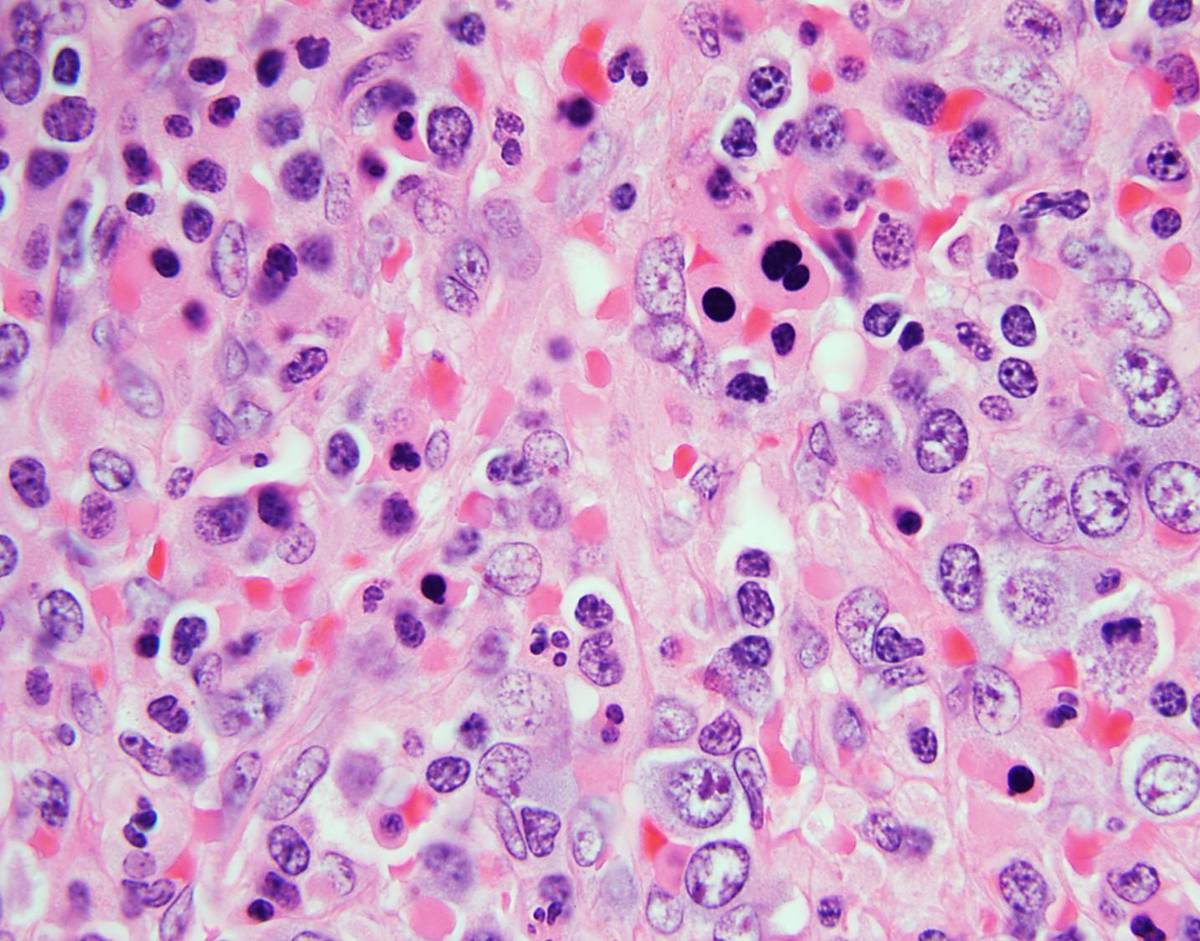

Bone Marrow Examination Bone marrow core needle biopsy (left posterior iliac crest) was fixed in Bouin solution. Bone marrow aspiration was sent for morphological evaluation, cytogenetic analysis and flow cytometry. • Core needle biopsy (hematoxylin and eosin) demonstrated marked erythroid hyperplasia, dyserytropoiesis and patchy interstitial pockets of large mononucleated cells with oval to folded nuclei, irregular nuclei contour and abundant amount of amphophilic cytoplasm. Moderate reticulin fibrosis was noted (MF-2, European Myelofibrosis Network) • Wright- Giemsa stained aspirate smear were of limited quality demonstrating 3% myeloblasts, promonocytes, atypical monocytes and erythroid hyperplasia with significant dyserythropoiesis. No Auer rods were present. Splenectomy Splenomegaly: 12.6 x 5.0 x 3.0 cm, 137 gms. Unremarkable capsular surface and homogenously red and congested parenchyma. Representative sections submitted for flow cytometry, cytogenetics, molecular studies and permanent sections (formalin fixed/ paraffin embedded). • Hematoxylin and eosin (H&E) stained slides showed expanded red pulp with extensive and markedly left-shifted extramedullary hematopoiesis (EMH) consisting of a mixture of left-shifted erythropoiesis, left-shifted myelopoiesis, occasional megakaryocytes and rare blast cells. White pulp appeared decreased and morphologically unremarkable. • Wright-Giemsa stained touch preparations show extramedullary hematopoiesis with erythroid predominance showing dysplastic features. Scattered blasts were present, promonocytes and monocytes including atypical forms were identified. Remaining myeloid elements showed progressive maturation

Bone Marrow Biopsy • IHC analysis: Blasts (3%) were positive for CD34, with a subset showing CD117 positivity. Marked erythroid hyperplasia was highlighted by E cadherin. • Flow cytometric analysis detected 1.1% myeloblasts, a minute population of hematogones and increased monocytes with a spectrum of maturation. Splenectomy • IHC analysis: CD34 highlighted rare blasts. CD61 highlighted rare megakaryocytes. Glycophorin A and E-cadherin showed erythroid elements. CD33/CD117 demonstrated left shifted myelopoiesis. CD20 demonstrated a relative decrease in white pulp. Increased CD56+ small lymphocytes were present. • Flow cytometric analysis detected immature precursor cells, as defined by CD34 or CD117 expression (3.4% and 6.1%, of gated events respectively).

| Spleen, 100X | ![]() |